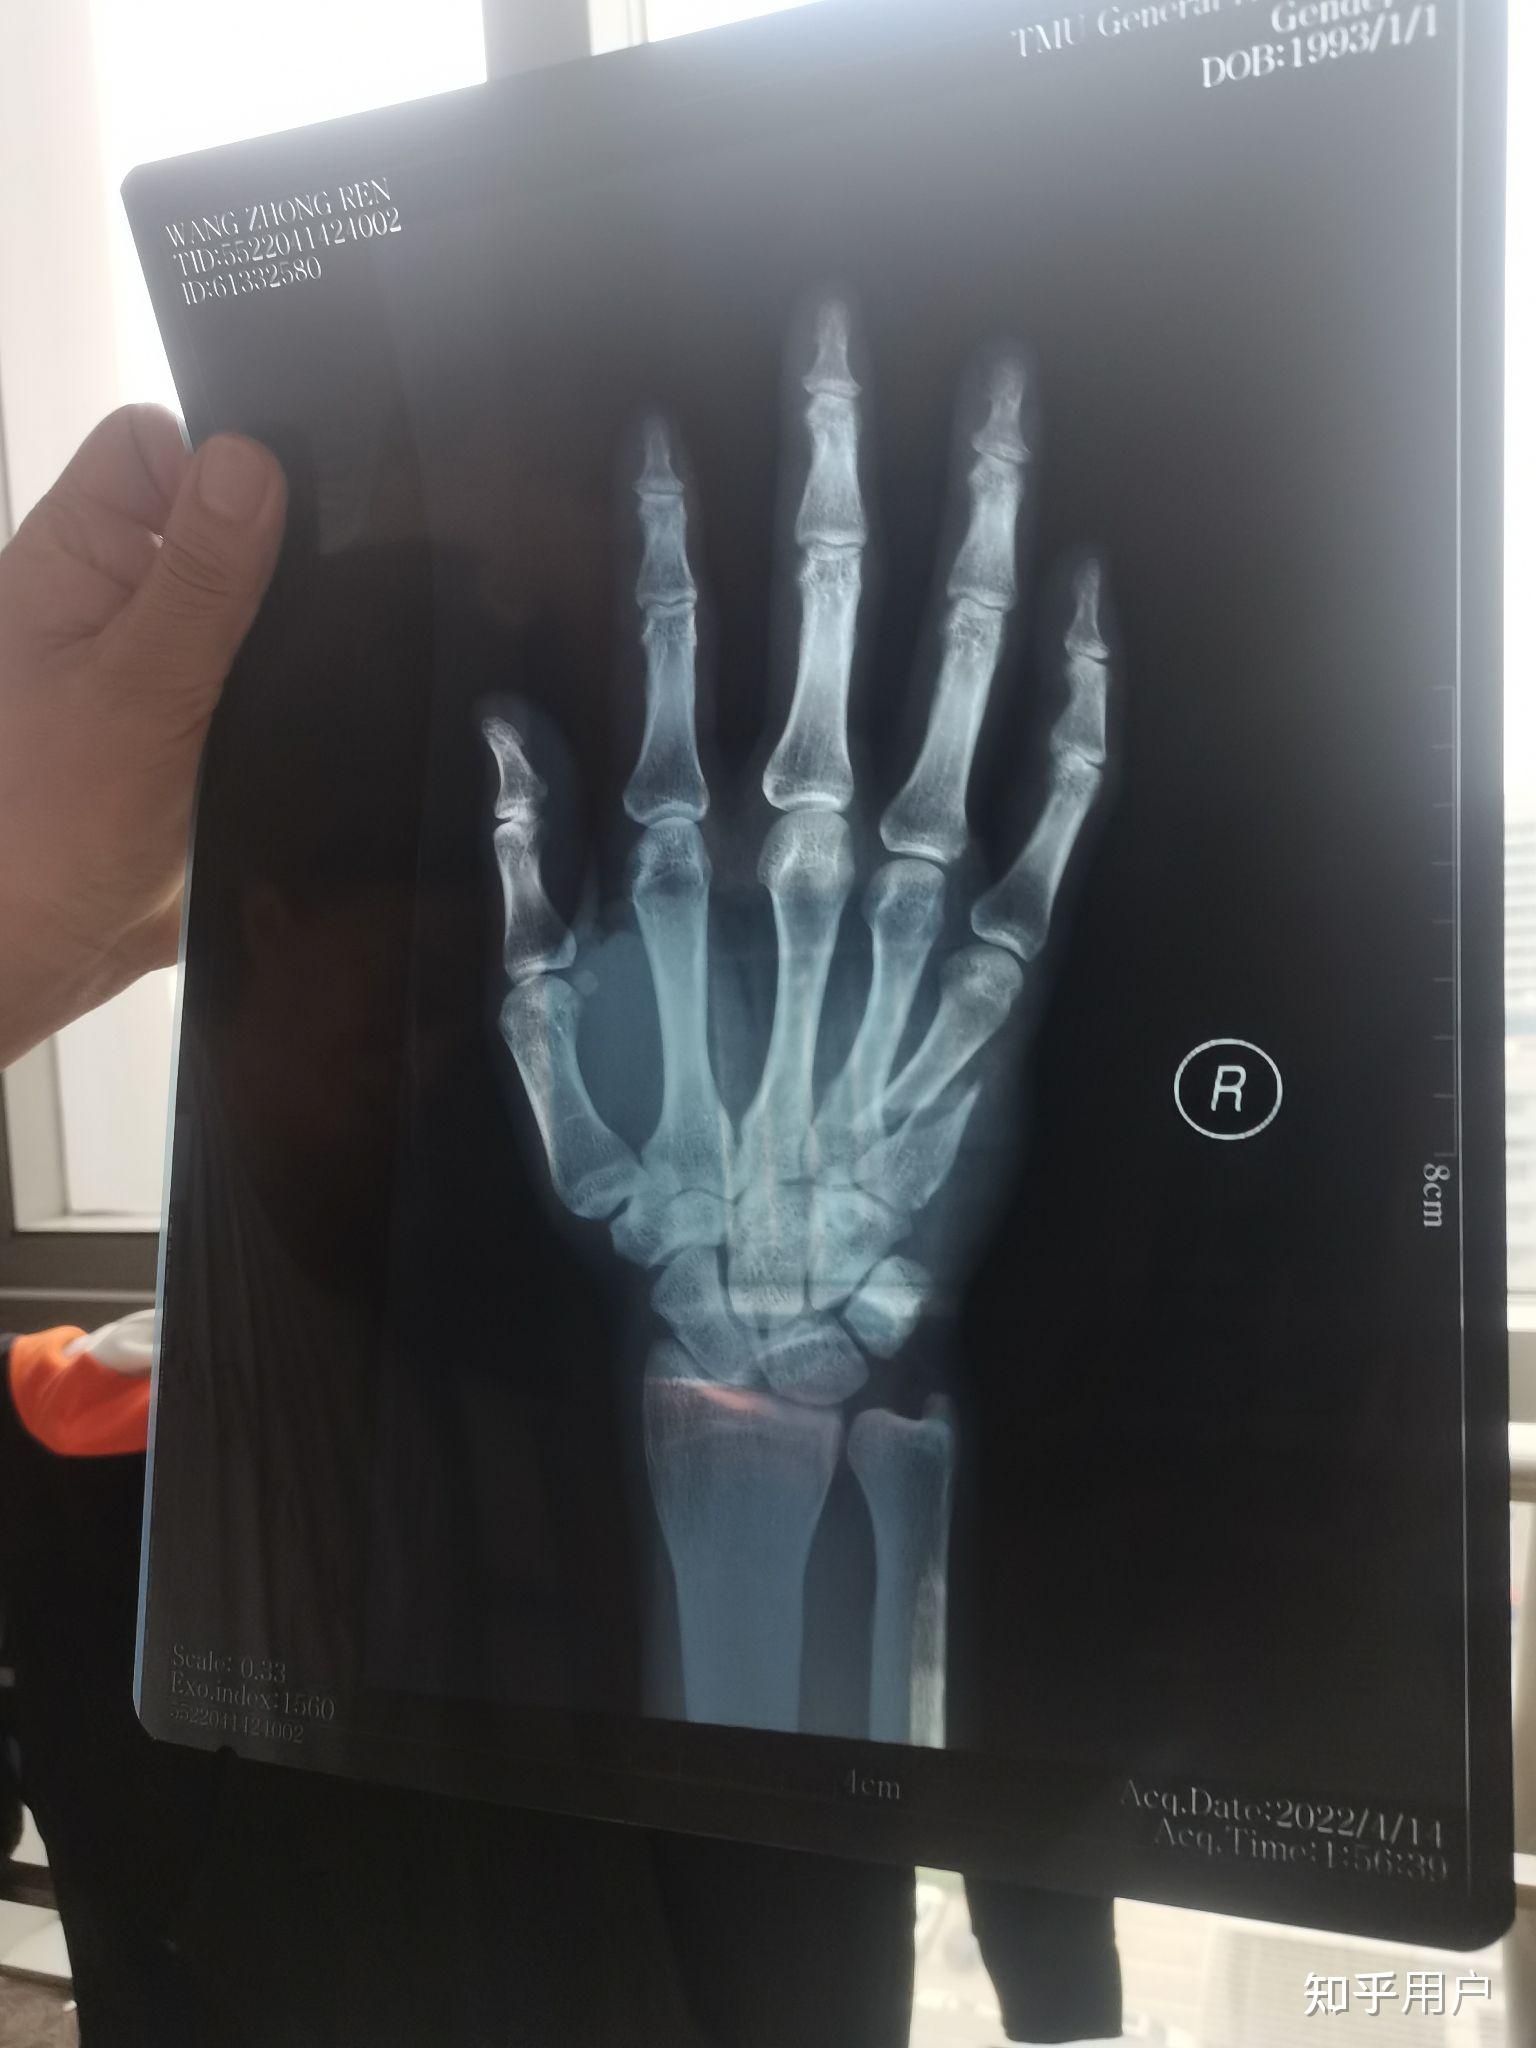

右手第四掌骨骨折保守治疗的第16天恢复的是否不太理想